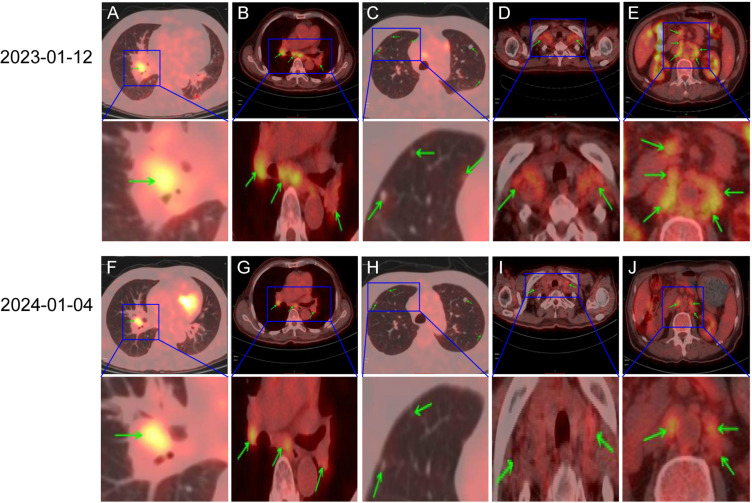

Envafolimab is a novel inhibitor for programmed cell death protein-ligand 1 (PD-L1) that can be administered subcutaneously. It has been found to be effective and safe in the treatment of advanced high microsatellite unstable (MSI-H) / mismatch repair deficient (dMMR) solid tumors. Currently, the efficacy of programmed cell death protein-1 (PD-1) / programmed cell death protein-ligand 1 (PD-L1) inhibitors in the treatment of microsatellite stable (MSS) tumors is not clear. We report a case of advanced colon cancer with MSS metastases in bilateral clavicle, mediastinum, retroperitoneum, bilateral hilum, and left side of thoracic 11/12 vertebral body. After 8 months of Envafolimab treatment, there was a significant reduction in metastatic lesions. As of February 1st, 2024, the patient exhibited no significant adverse reactions. The current efficacy evaluation was the partial response (PR), and the overall survival (OS) was more than 12 months. Considering the safety and efficacy of Envafolimab observed in our case, we believe that Envafolimab may be a promising drug for the treatment of MSS metastatic colon cancer.

Abstract Image